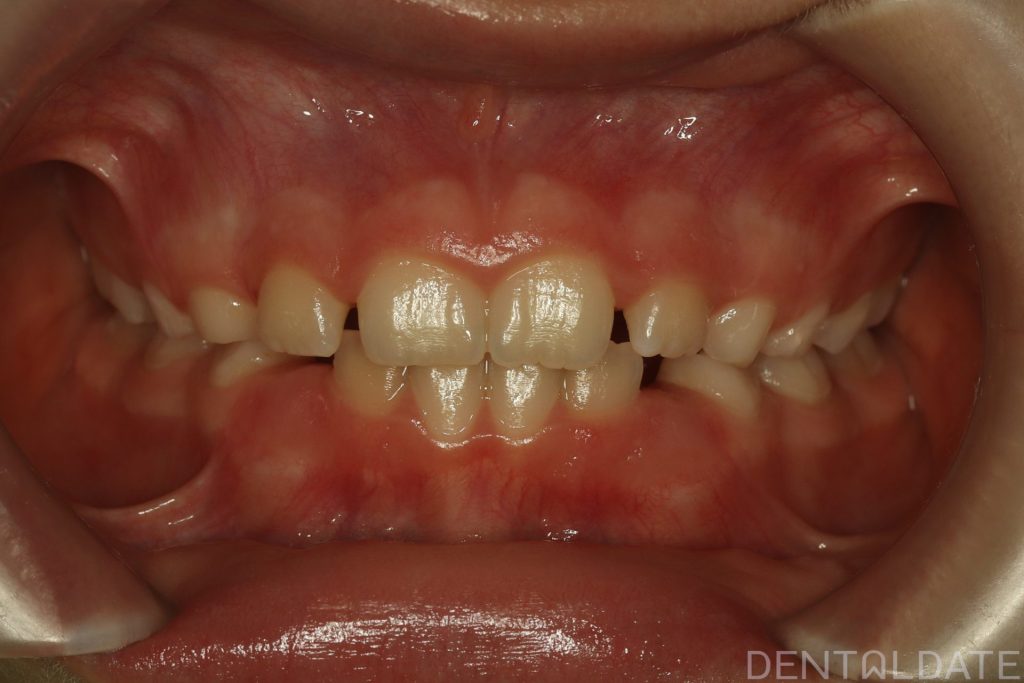

Parents sought an orthodontic consultation due to concerns about the aesthetics of their child’s smile.

To achieve harmony between function and aesthetics, a Haas appliance was used, followed by a myofunctional appliance.